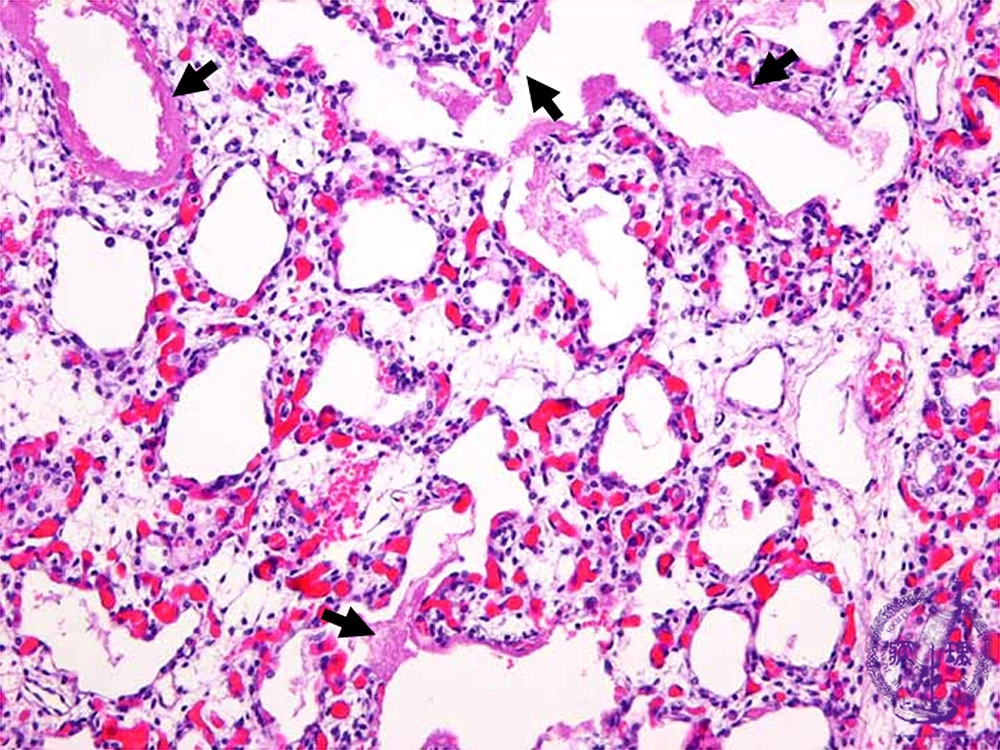

- (6)Hyaline membrane disease・Neonatal respiratory distress syndrome

Microscopic view (H&E); The air spaces are lined by an irregular layer of homogenous, finely granular eosinophilic material. It is most commonly seen in premature infants (less than 34 weeks gestation) who are deficient in alveolar surfactant. The alveolar ducts are diffusely lined by hyaline membrane composed of fibrin with necrotic epithelial cells. The alveolar epithelial cells and bronchiolar epithelium are injured and necrotic. The administration of exogenous surfactant at birth is very effective, and it is now uncommon for premature infant to die from RDS.